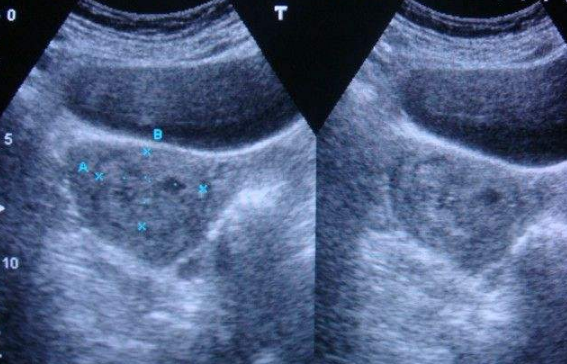

雙角子宮圖片

雙角子宮 (9)